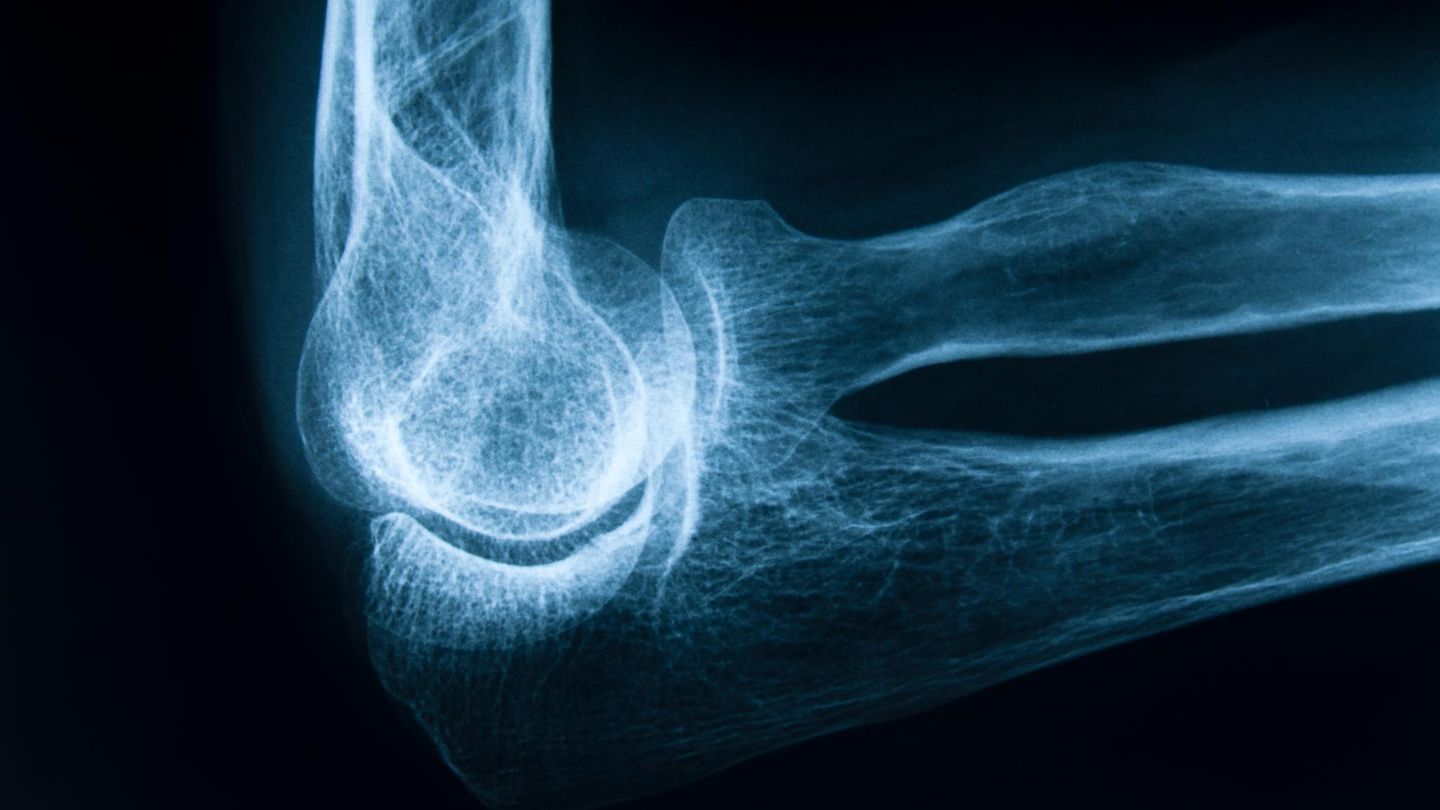

Die Frage "wie stark sind meine Knochen noch", beschäftigt viele, wenn sie altern. Inzwischen hat sich der Blick der Medizin auf den Knochenschwund stark verändert

© GeorgHanf/ Getty Images / Getty Images